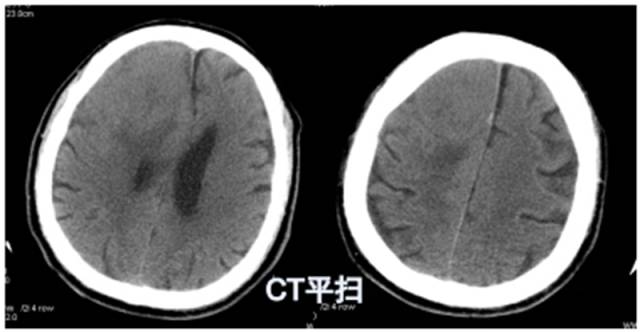

CT平扫(骨窗 脑窗)

病例:男性,30岁,头痛2月

CT平扫